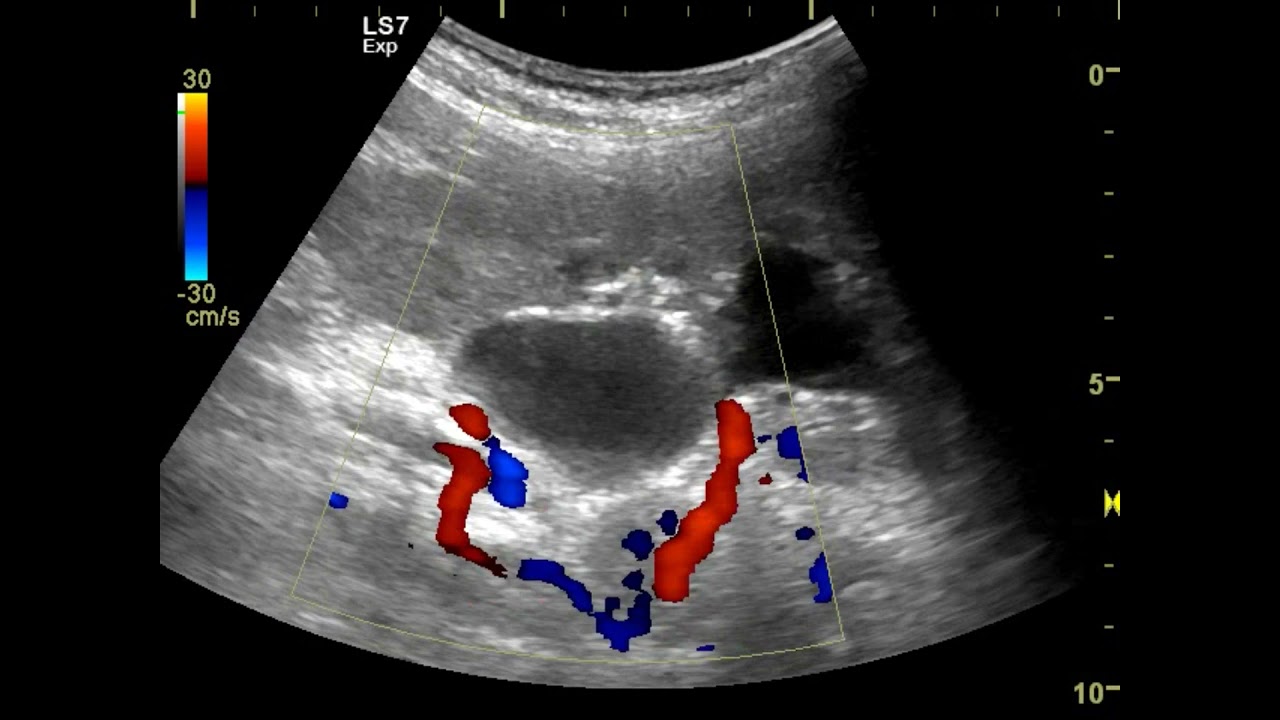

Гидронефроз почки после операции